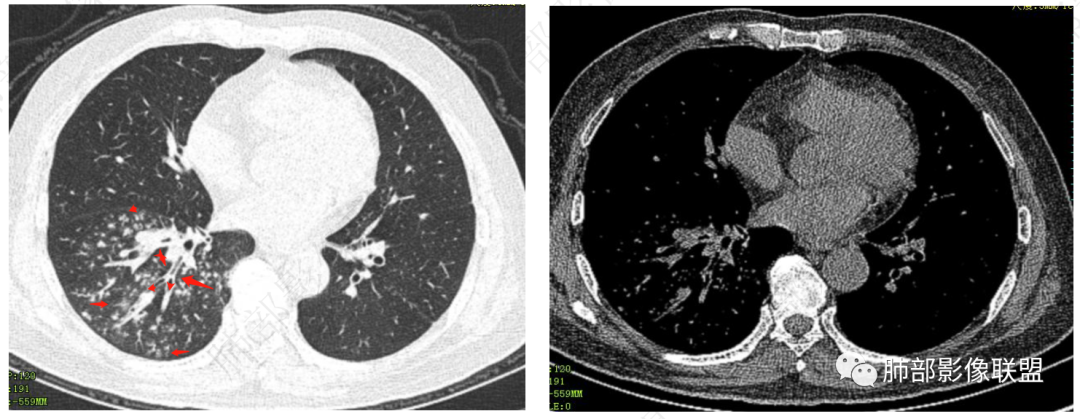

右肺下叶多发腺泡结节影,边缘部分模糊,伴树芽征,支气管壁增厚,10天复查腺泡结节有吸收变淡,病变内出现多发囊状影,考虑感染性病变,金葡?真菌?

中年男性,咳嗽咳黄脓痰一周,有糖尿病,肾病病史,长期使用激素血象白细胞自然会升高,但CRP明显升高。降钙素原不高,肺泡灌洗液阴性。右下肺沿支气管分布腺泡结节影,少于树芽征,小实变影,支气管壁轻度增厚,考虑感染性疾病,从病灶形态来看气道来源,复查病灶有小空洞形成,病灶明显吸收。考虑气道金葡菌肺炎,鉴别奴卡菌

南边:急性、慢性,看树芽征的边缘。NTM也好,结核也好,他们属于慢性病变、反复发作,毒力不那么强,所以他相对来说发展速度非常慢,病变以增殖为主,因此他的边缘比较清楚,也可以引起支气管增厚。但是金葡菌是急性感染,所以他的边界是非常模糊的,外围磨玻璃非常多。

病变区支气管壁弥漫增厚,远端树芽征,周围GGO——渗出

4.金葡——小气道、肺泡,早期小叶性肺炎:树芽征、腺泡结节等

小气道树芽征、周围渗出——GGO